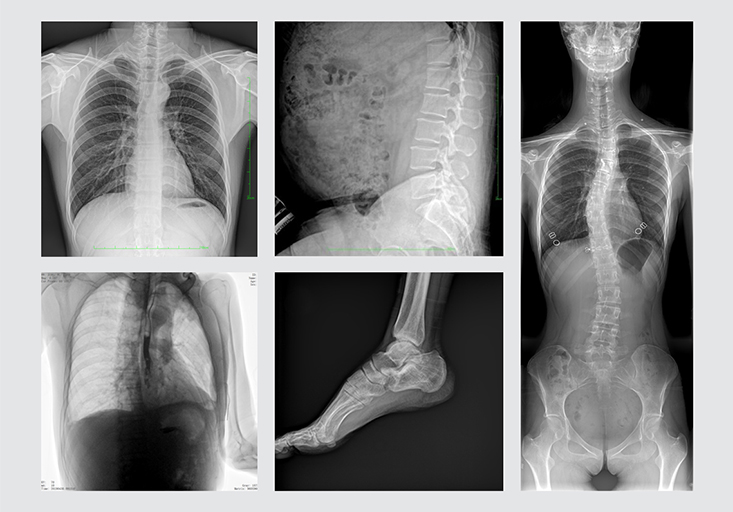

清晰的临床图像